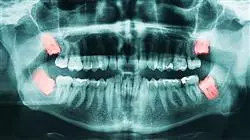

Las enfermedades gingivales y periodontales se encuentran entre las afecciones más comunes de la consulta odontológica. Debido a que cada vez son más las personas que requieren de la asistencia médica con el fin de atender estas condiciones, contar con personal odontológico especializado es imprescindible. En TECH Global University elaboramos este Grand Master en Periodoncia, Implantología y Cirugía Bucal, un programa diseñado para ofrecerte una capacitación completa sobre los últimos métodos y tecnologías de abordaje en este campo. De esta manera, adquirirás el bagaje conceptual y las competencias técnicas más especializadas y ofrecerás tratamientos más específicos a cada paciente.

Nuestro Grand Master te capacitará para asistir las diferentes áreas de la periodoncia, implantología y cirugía bucal. Podrás revisar la anatomía macroscópica y microscópica del periodonto, así como los maxilares y tejidos vinculados con el fin de emitir un diagnóstico y determinar el tratamiento óptimo en cada caso. Asimismo, estudiarás con detalle las patologías que pueden afectar esta zona y la forma de intervención más apropiada, siempre teniendo el uso del láser como un método aliado en estos procedimientos. Asimismo, contarás con el acompañamiento de expertos en el área que orientarán tus estudios y favorecerán la exploración de tus capacidades basándose en el mejor material didáctico y el estudio de casos clínicos reales. Esta capacitación impulsará el crecimiento de tu carrera profesional y te guiará hacia un mejor futuro laboral.